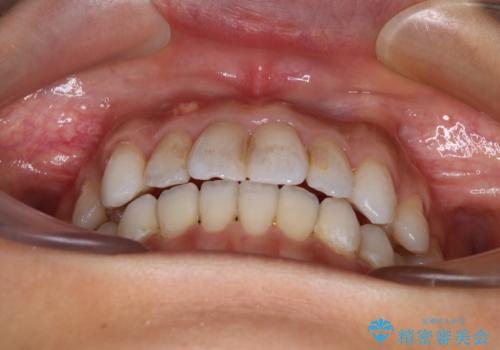

【モニター】開咬を治したい インビザラインによる矯正治療

- 上下前歯の開咬とデコボコを気にして来院された患者様です。

開咬(オープンバイト)はインビザラインによる矯正治療がワイヤー装置と比べて圧倒的に有利であるため、インビザラインによる矯正治療を行うこととしました。

通院されなかった時期があって治療期間が長くなったり、奥歯に抜歯が必要な歯があったりと、治療は一筋縄にはいきませんでしたが、何とか治療を終えることができました。